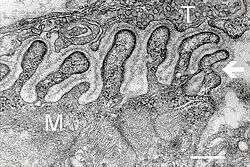

Electron micrograph showing a cross section through the neuromuscular junction. T is the axon terminal, M is the muscle fiber. The arrow shows junctional folds with basal lamina. Active zones are visible on the tips between the folds. Scale is 0.3 μm. Source: NIMH